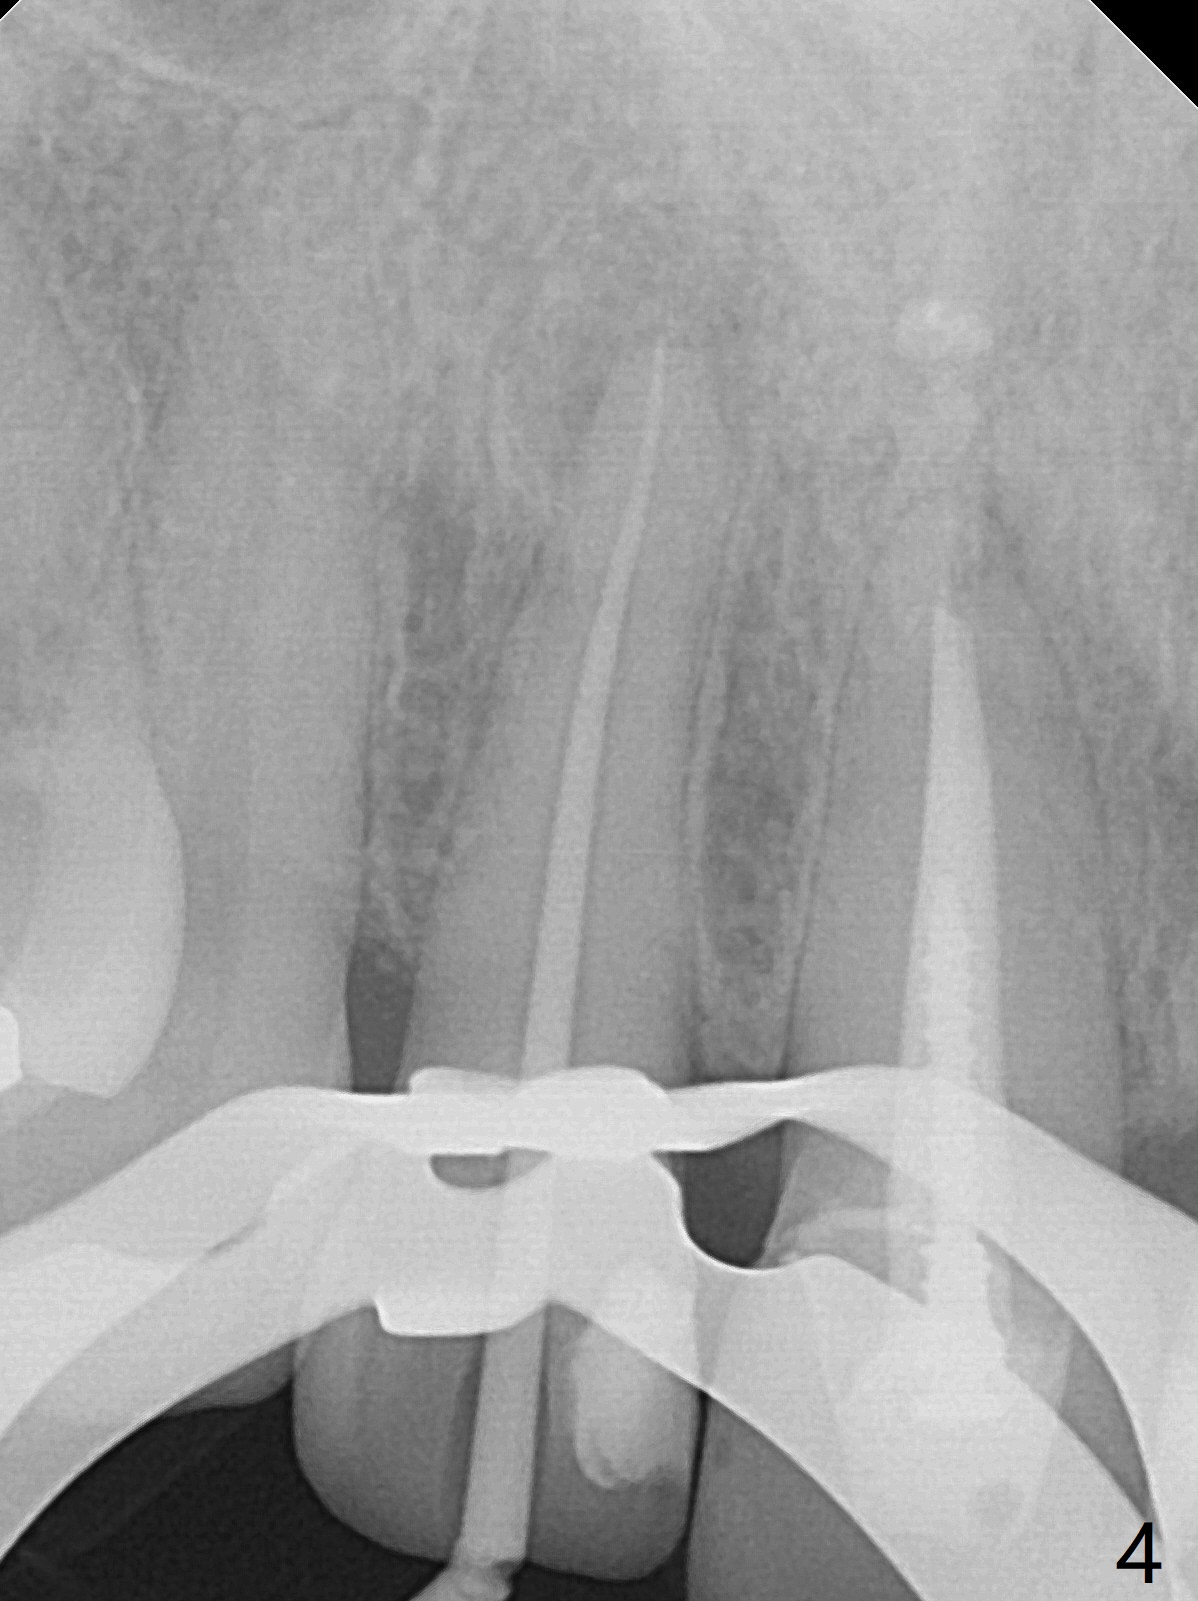

A 46-year-old woman requests a crown for the discolored tooth #7 (Fig.1,2) with mesiolingual composite (Fig.3 C) and periapical radiolucency (*). After RCT (Fig.4,5) with sodium hypochlorite, the tooth #7 is whiter than the ML composite (Fig.6,7). The patient returns 1 day post RCT for in house internal and external bleaching (Fig.8) with 35% hydrogen peroxide gel closed in the canal when she leaves. Three weeks later, the lateral incisor has the shade as the neighboring natural teeth (Fig.9,10). After the lightest shade composite placed in the canal and the access hole (Fig.11), the lateral looks better than the central with a crown and cervical discoloration (Fig.12).